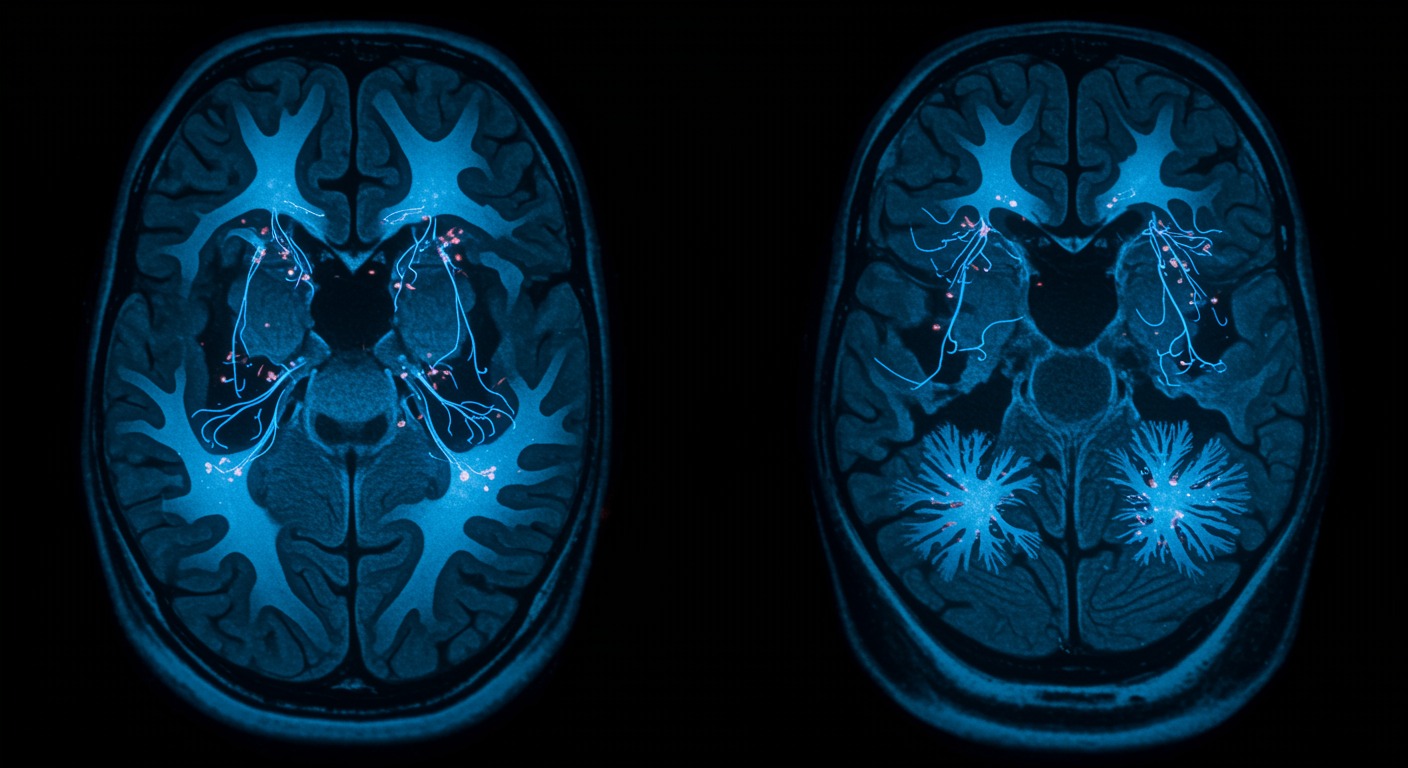

The Biology of Loneliness: How Social Isolation Damages Your Body